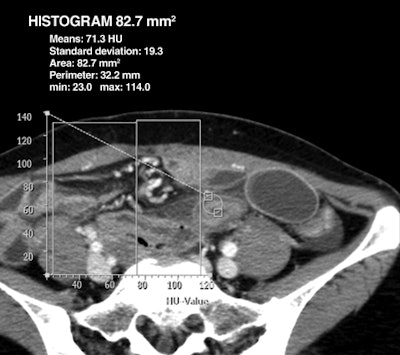

| Woman, 39 years old, with small-bowel obstruction secondary to adhesion. Axial contrast-enhanced (above) and unenhanced (below) CT images through lower abdomen show thickened small bowel with preserved bowel wall enhancement and perilesional mesenteric haziness. Maximal attenuation of ROI on contrast-enhanced CT image above is 114 HU, and subtraction value of maximal attenuation of ROI between contrast-enhanced (above) and unenhanced (below) images is 60 HU at thickened bowel lesion. At surgery, peristalsis and arterial pulsation of bowel were preserved, and there was no bowel lesion of discoloration. Images republished with permission of the American Roentgen Ray Society. |